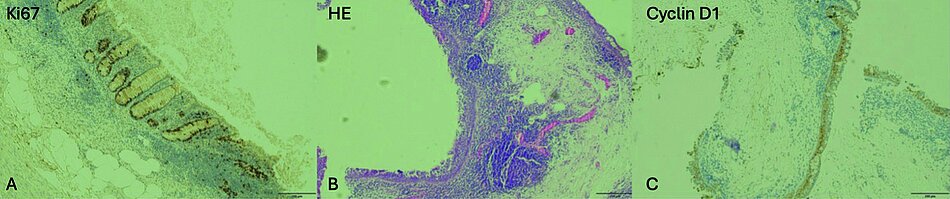

Histologie der Probeexzision (PE) zum Ausschluss eines follikulären Bindehautlymphoms: Zusammenfassung: Bindehaut-PE (Auge rechts) mit einem umschrieben vermehrten lymphozytären Infiltat. Zur weiteren Charakterisierung der lymphozytären Infiltrate erfolgten immunhistochemische Zusatzanalysen. Das immunhistochemische Expressionsmuster zeigt regelrechtes lymphatisches Gewebe mit einzelnen Keimzentren ohne gesteigerte Hinweise für Infiltrate eines Lymphoms. Die Veränderungen sind somit als reaktiv zu bewerten. Es besteht kein Anhalt für Malignität (siehe Abb. 1).